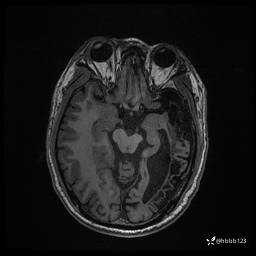

患者男,43岁。

简要病史:癫痫患者复诊,昨日发作5-6次,建议住院进一步治疗。

入院完善脑癫痫组合序列:

T2: